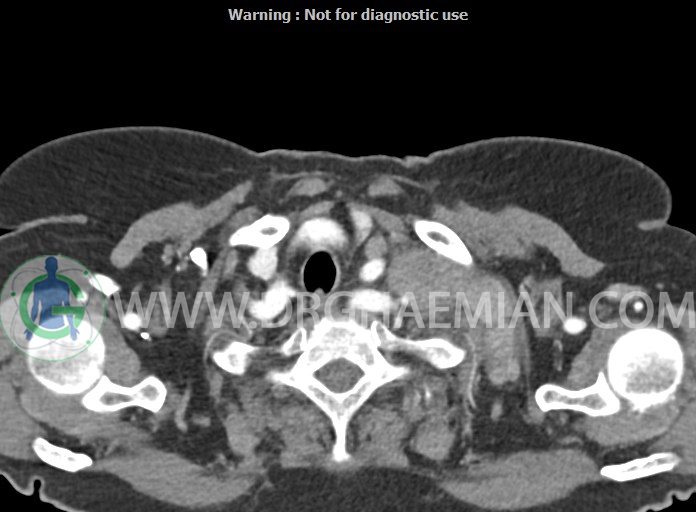

در سی تی اسکن اسپیرال از گردن با تزریق (مولتی دیدکتور 16 با مقاطع ظریف و بازسازی های ساژیتال و کرونال):

– تصویر توه های نسج نرمی oval shape متعدد با Enhancement تقریباً هوموژن، قرار گرفته در سمت چپ گردن، در لول غضروف کریکوئید با اثر فشاری شدید و compression ورید ژوگولار، با گسترش تحتانی به اینفراکلاویکولار چپ، به حداکثر ابعاد 28x50mm (با Enhancement مختصر هتروژن در این توده)

در درجه اول مطرح کننده لنفادنوپاتی متاستاتیک مطرح می باشد بالین، تومورهای منشأ گرفته از غلاف عصبی زنحیره سمپاتیک چپ گردنی، شبکه براکیال و لنفوم نیز در DDX قرار دارند. لذا نمونه برداری بافتی جهت بررسی بیشتر توصیه می شود.

– اسکولیوز مهره های سرویکال با تحدب به راست، احتمالاً در زمینه اثر فشاری توده های مذکور

مشهود است.